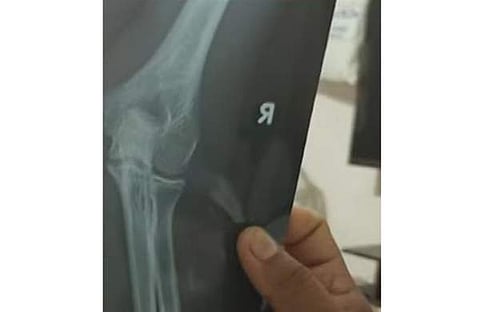

ഉടന് തന്നെ പാറശാല താലൂക്ക് ആശുപത്രിയില് കൃഷ്ണ കുമാര് ചികിത്സ തേടി. കൈ ഒടിഞ്ഞതിനെ തുടര്ന്ന് കുട്ടിയുടെ കൈയില് പ്ലാസ്റ്റര് ഇട്ടിട്ടുണ്ട്. സംഭവത്തില് സ്കൂള് അധികൃതര് രണ്ടു വിദ്യാര്ഥികള്ക്കെതിരെ പാറശാല പൊലീസില് പരാതി നല്കിയിട്ടുണ്ട്.